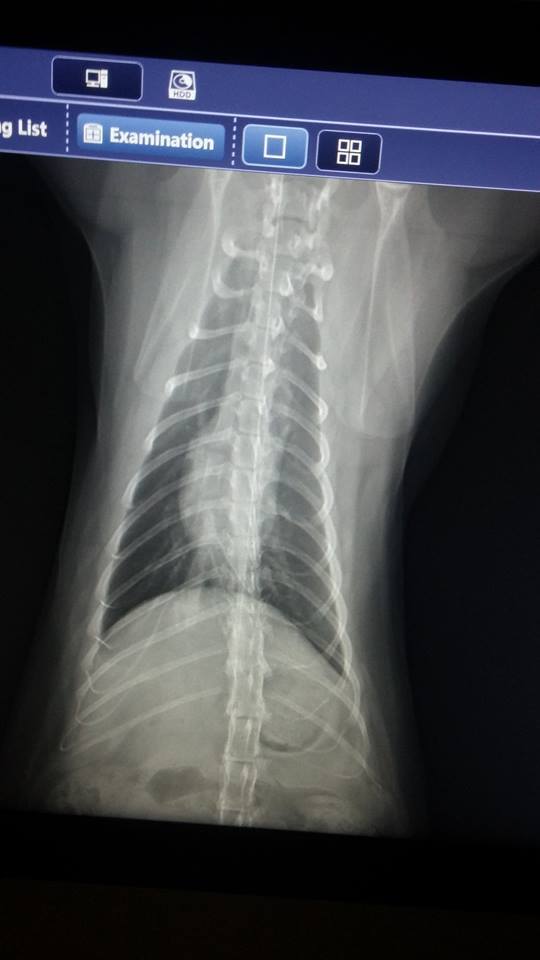

今日主要是定期複診與照X光,

經由診斷與X光片的結果,

小君子的牙齒狀況OK,

但胸腔還有一點分泌物,

故繼續吃兩個禮拜抗生素。